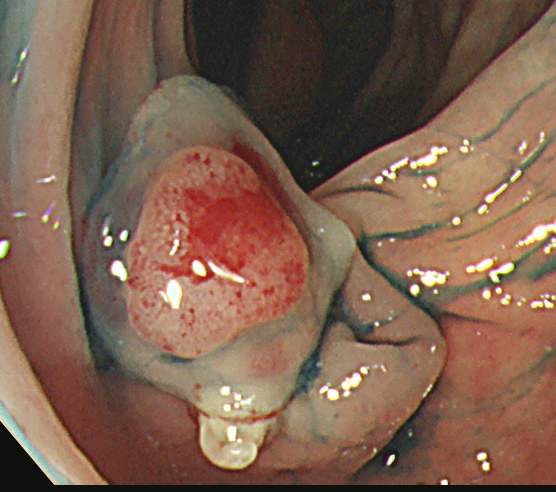

実際の写真です。

「生切り」なので、当然、内視鏡中(切除時)は出血します(患者さんが不安になります)。しかし、出血は数分で止まり、晩期出血は、まずありません。

コールド法で切除された検体は「目玉焼き」のようになります。「黄身」が病変で、「白み」が周囲の正常組織(余白、マージン)です。

腫瘍の取り残しを防ぐために「白み(余白)の大きな目玉焼き」にすることが、コールド法の最大のポイントであり、技術的に最も難しい部分です。